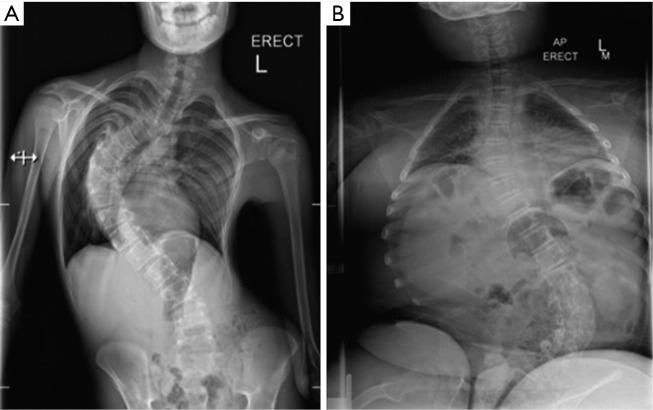

در بعضی از بیماران، بهویژه در نوع دوشن، مشکلات شناختی خفیف، اختلالات یادگیری یا تأخیر در گفتار نیز گزارش شده است. علاوه بر این، مشکلات گوارشی، دشواری در بلع و انحراف ستون فقرات (اسکولیوز) ممکن است در طول پیشرفت بیماری بروز پیدا کنند و نیازمند پیگیری و درمان باشند.

برای بررسی درگیری سایر اندامها، آزمایشهای تکمیلی نیز انجام میشود. تصویربرداری MRI از عضلات میتواند الگوی درگیری عضلانی را نشان دهد. بررسی قلب با نوار قلب و اکوکاردیوگرافی و ارزیابی عملکرد ریه با تستهای تنفسی، بخش مهمی از فرآیند تشخیص و پایش بیماری هستند.